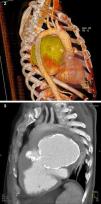

The patient then underwent computed tomography (CT) angiography, which showed a large pseudoaneurysm adjacent to the mitral-aortic intervalvular fibrosa (MAIVF), communicating mainly with the left ventricle (Figures 2 and 3), and compressing the pulmonary trunk, left pulmonary artery, left main bronchus, and the bronchovascular structures of the lingula and lower lobe of the left lung. There was also deviation of mediastinal structures to the left.